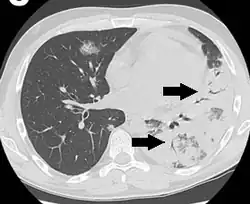

An air bronchogram is defined as a pattern of air-filled bronchi on a background of airless lung.[1]

In pulmonary consolidations and infiltrates, air bronchograms are most commonly caused by pneumonia or pulmonary edema (especially with alveolar edema).[2][3]